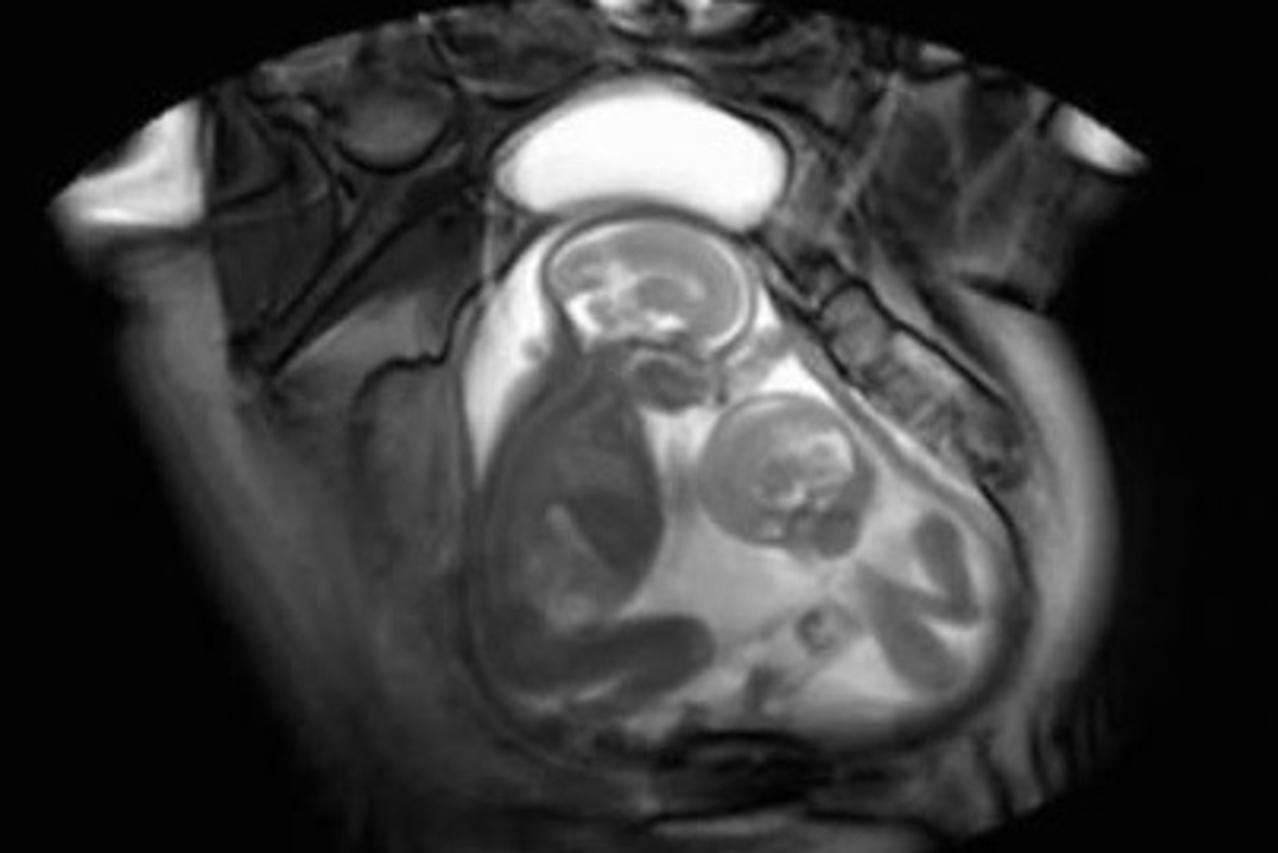

Rivalstvo i prije rođenja: Ovako se blizanci gurkaju u maternici

blizanci maternica

Screenshot: YouTube

Rivalstvo braće i sestara može početi i prije rođenja, a to zorno pokazuje snimka znanstvenika iz Londona na kojoj se vidi "tučnjava" blizanaca u maternici

Na snimci se jasno vidi kako manji blizanac gura svoju nogu u prostor većeg, kao da ga pokušava odgurnuti ili udariti, iako se sa sigurnošću ne može reći što se zaista događa između njih.

– Ako imate dva fetusa u maternici, nemoguće je da oni stalno budu na svojim mjestima – kazala je ginekologinja dr. Marjorie Greenfield koja prikazano kretanje ne bi nazvala tučnjavom, ali joj je snimka zanimljiva.

– Blizanci se već stoljećima udaraju u maternici – kaže Greenfield te dodaje da mi to nismo prije mogli doživjeti na ovaj način.